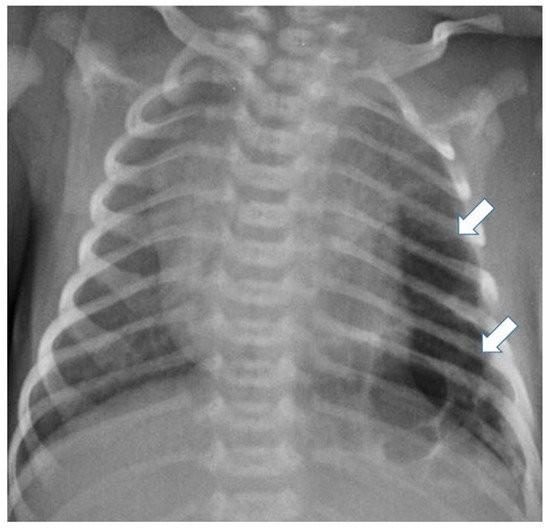

3.4.1. Pulmonary Underdevelopment

3.4.2. Congenital Pulmonary Airway Malformations